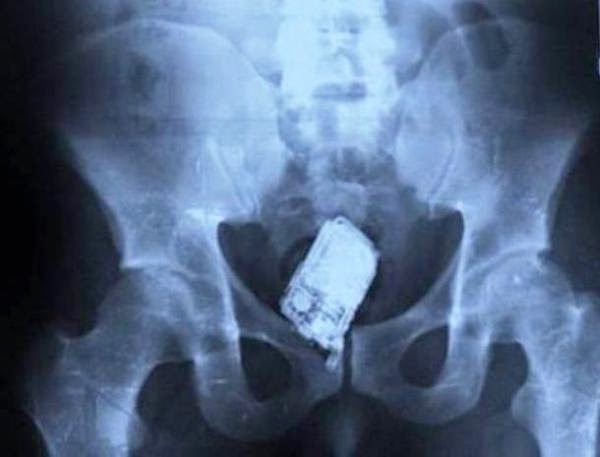

Un teléfono móvil.